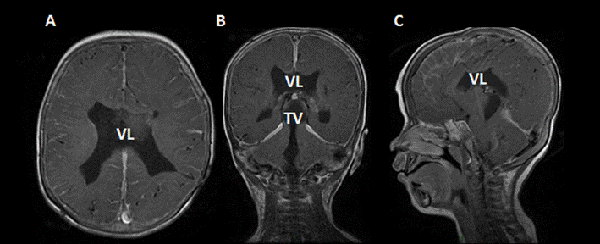

Reingreso a los 26 días postquirúrgicos con fiebre, irritabilidad, llanto persistente, rechazo al alimento; y signos de hipertensión endocraneana. Se tomó muestra de líquido cefalorraquídeo (LCR), en el cual se aíslo Enterobacter complex (E. hormaechei), se realizó resonancia magnética de cerebro con contraste, donde se evidenció realce a nivel ependimario compatible con ependimitis (Figura 1). Se colocó DVE y realizó un nuevo tratamiento con meropenem y colistin endovenoso asociado a tratamiento intraventricular con colistin. La dosis de colistin fue ajustada en base a el cálculo por imágenes del volumen ventricular. Se administró una dosis diaria de 4 mg de colistin, con posterior lavado de la guía con 1 ml de solución fisiológica. Durante la internación se realizaron 4 procedimientos endoscópicos que consistieron en lavados ventriculares, aspiración del contenido purulento intraventricular, acueductoplastia con colocación de catéter de DVE entre el tercer y el cuarto ventrículo (tras constatar re obstrucción del acueducto) con el objetivo de mantener la permeabilidad de la misma y de esta manera asegurar la llegada de antibiótico intraventricular al cuarto ventrículo. Se tomaron muestras del LCR cada 72-96 horas, utilizado como referencia de evolución las características citofisicoquímicas, el valor de ácido láctico y los cultivos. Luego de 21 días de tratamiento antibiótico, la paciente mejoró clínicamente y los parámetros infecciosos de LCR se normalizaron. Se retiró el catéter trans acueductal bajo visión directa por endoscopia y en el mismo procedimiento tras observar oclusión del ostoma previo, se repitió el procedimiento de TVE que no fue exitoso, por lo que se colocó una DVP presión fija media. No se registraron complicaciones asociadas en los procedimientos endoscópicos.

Actualmente tras 14 meses de seguimiento, la paciente se encuentra asintomática y en el control de resonancia magnética realizada a los 12 meses de post quirúrgico donde se observó disminución del tamaño ventricular ausencia de tabiques interventriculares, y ausencia de realce tras la administración de contraste (Figura 2).

Figura 1: RM de encéfalo prequirúrgica: A) corte axial, B) coronal y C) sagital, ponderado en T1 con contraste. Se observa dilatación del sistema ventricular, ausencia de septum pellucidum, adelgazamiento de sustancia blanca periventricular y cuerpo calloso, con realce ependimario compatible con ventriculitis (flecha).

Figura 2: RM de encéfalo realizada a los 12 meses post quirúrgico de la colocación de la DVP: A) corte axial, B) coronal, C) sagital, ponderado en T1 con contraste. Se observa disminución del tamaño ventricular en comparación con resonancia previa, sin realce ependimario tras la administración de contraste.